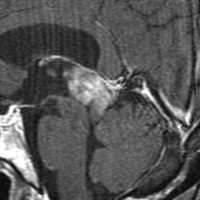

水都症で発症した20代の女性です。のう胞を含む境界明瞭な松果体腫瘍で,松果体細胞腫のようにもみえます。しかし,中脳視蓋と左視床に浸潤像が疑われます。OTAで中脳内部に食い込むものも全摘出しました。術後2年で軽度の眼球上転障害を残していますが復職できました。

細胞密度が高く,腫大核を有する異型細胞が充実性に増殖する腫瘍です。でも一部で,pineocytomaに相当する分化像を示す部分があり,NF部分的陽性が多くグレード IIと判断されました。しかし,手術所見で視床浸潤がみられ,MIB-1 5-7% (左の画像)であり,WHOの規定するMIB 5%以上の高リスクPPTIDとも言えます。

この病理診断からはかなり迷うのですが,脳脊髄照射 24Gy/12分割,腫瘍局所総線量 54Gy/27分割の放射線治療を行いました。脳脊髄照射を加えた最終的な判断は,細胞密度がかなり高くMIB 10%程度の部分像を有するPPTIDであったからです。